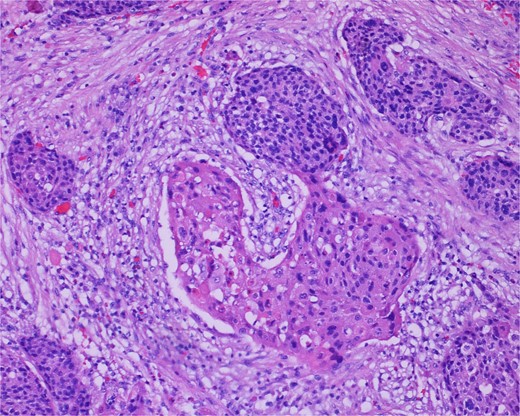

High-power view of the neoplasm shows focal merging of the high-grade neoplasm with squamoid differentiation.

The gross specimen consisted of multiple particles of gray friable tissue, aggregating to 58 g, 8 × 8 × 4 cm in greatest dimensions. Representative sections were submitted for histological processing and subsequent microscopic study in 12 cassettes. Histopathologic examination of the curated bladder mass revealed sheets of high-grade malignant urothelial carcinoma with adjacent areas of neuroendocrine-like differentiation (Fig. 1). There were extensive areas of tumor necrosis, extending into the muscularis propria. Merging of divergent differentiated cells was discernible in some areas (Fig. 2). Immunohistochemical stains of malignant neuroendocrine cells (Fig. 3) were positive for CD56, NSE, synaptophysin, INSM1, GATA-3 (scant), and Ki-67 (>80%), but negative for chromogranin A, TTF-1, p53, uroplakin, and Pan-CK. The malignant urothelial cells were positive for GATA-3 (Fig. 4). The histologic and IHC profiles of the curated bladder mass were consistent with invasive high-grade urothelial carcinoma, with neuroendocrine carcinoma comprising ~30% of the malignant cells.